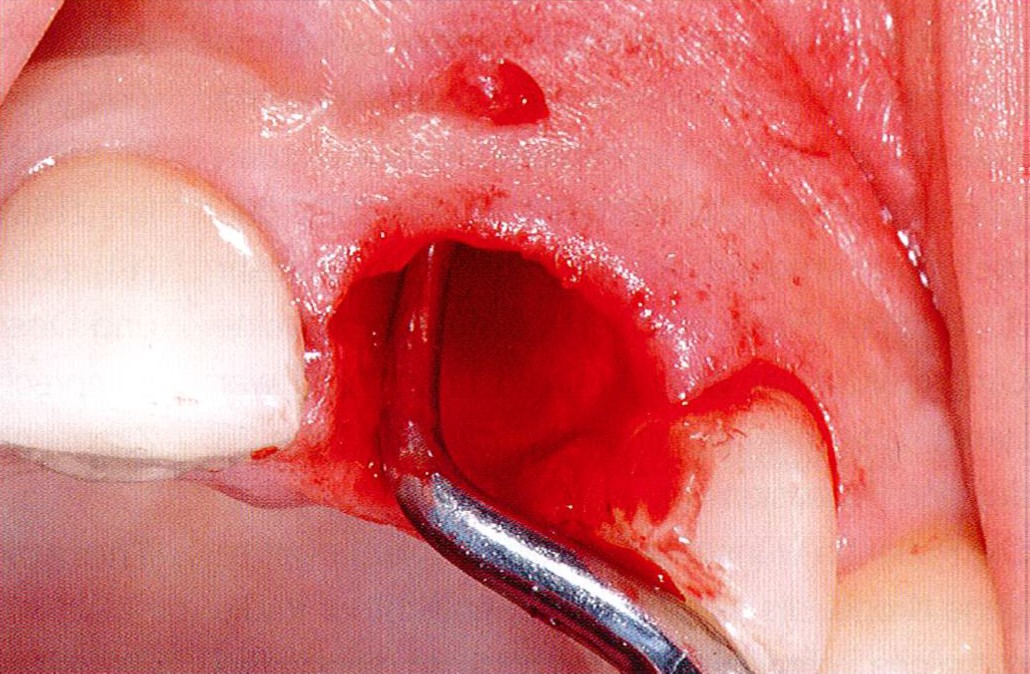

Longitudinal fracture on the root resected tooth 21 with visible buccal fistula